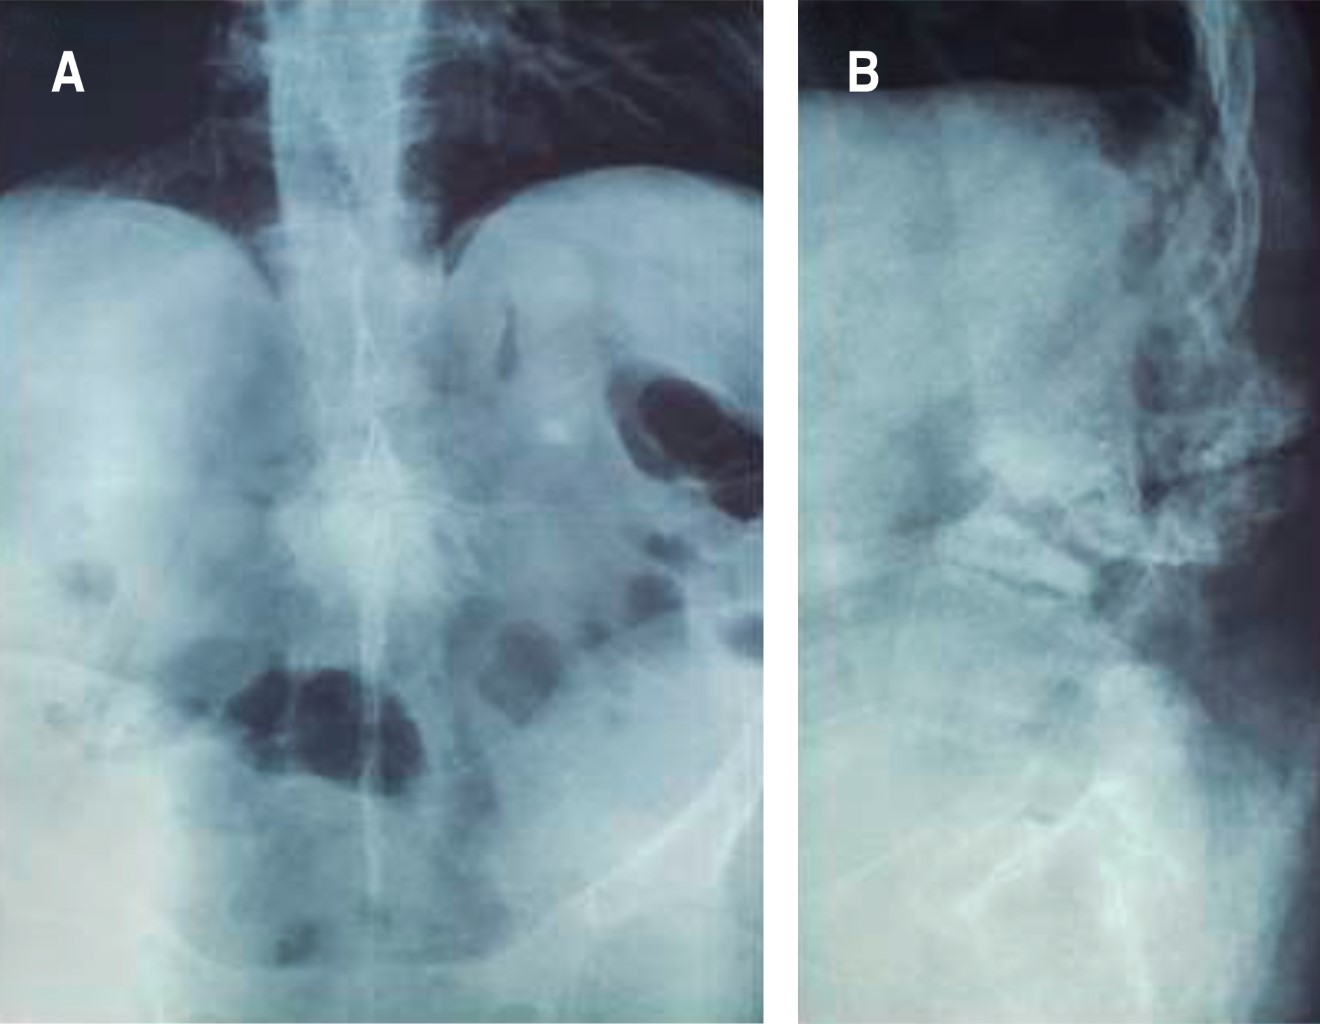

Masculino de 49 años, agricultor, obeso, tabaquismo por 30 años, dolor lumbar con aumento progresivo durante los últimos cinco años, intensidad 6/10 EVA, se intensifica con la movilización, se palpó lesión sólida en la línea media de la región torácica baja y lumbar alta, limitación de los movimientos del tronco, sin datos radiculares en extremidades inferiores (Figura 1). El paciente tenía estudio de HLA-B27 positivo. Estudios de imagen: columna toracolumbar en "caña de bambú", laterolistesis izquierda a nivel de fractura en cuerpo de L3, pseudoartrosis en L2-L3 y espondilolistesis L5-S1. (Figuras 2, 3 y 4).